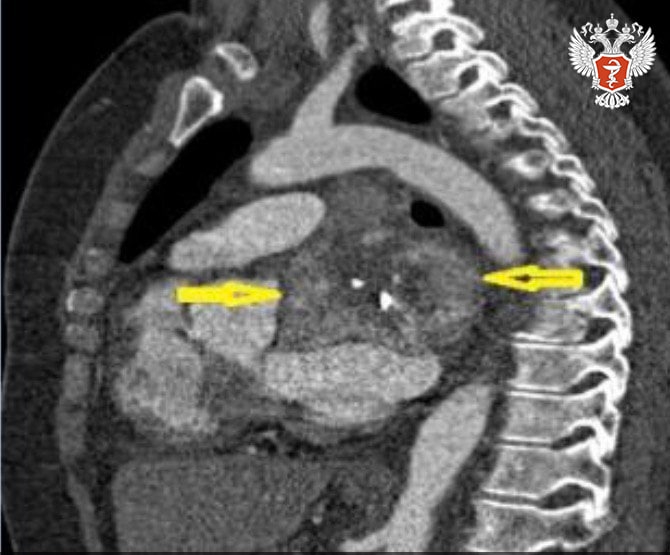

48-летняя пациентка обратилась в НМИЦ онкологии им. Н.Н. Блохина Минздрава России с диагнозом «параганглиома сердца». Опухоль поражала левое предсердие.

➡ Специалисты выяснили, что удалить опухоль стандартным способом с использованием бычьего ксеноперикарда невозможно.

Врачи решили провести аутотрансплантацию сердца — высокотехнологическую операцию, при которой орган пациента на время извлекают из грудной полости для удаления труднодоступной опухоли, а затем возвращают на место.